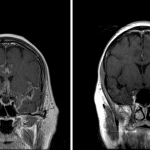

Indication: Altered mental status, history of melanoma

Findings

- Multifocal cortical T2/FLAIR signal hyperintensity and nodular cortical and leptomeningeal enhancement with gyral expansion, most avidly involving the bilateral parafalcine frontal lobes, right greater than left banks of the sylvian fissures, and along the superior vermis

- Diffuse nodular thickening and enhancement of the pial surfaces of the brainstem as well as involving the cerebellar tentorium bilaterally

- Few intermixed areas of T1 signal hyperintensity, particularly along the pial surface of the paramedian cerebral hemispheres

- No evidence of acute ischemia, hemorrhage, mass effect, or hydrocephalus

- Enhancing lesion in the right frontal sinus with otherwise mild scattered mucosal thickening of the paranasal sinuses

Diagnosis

- Leptomeningeal disease

Findings consistent with extensive leptomeningeal disease, most prominently along the bilateral medial frontal lobes and sylvian fissures, but also involving multiple structures in the posterior fossa. Given history, this appearance is thought most likely to represent tumor dissemination with granulomatous disease such as sarcoidosis, tuberculosis, and fungal infections considered less likely alternative diagnoses. Recommend correlation with CSF analysis and consideration of total spine MRI with and without contrast for further evaluation.

A few intermixed areas of T1 signal hyperintensity, particularly along the pial surface of the paramedian cerebral hemispheres, may represent associated trace hemorrhage or proteinaceous debris.

No evidence of acute ischemia, organized hematoma, mass effect, or hydrocephalus

Enhancing lesion in the right frontal sinus which may represent a polyp or possibly localized fungal colonization.